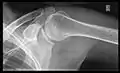

Imaging of the shoulder includes ultrasound, X-ray and MRI, and is guided by the suspected diagnosis and presenting symptoms.

Conventional x-rays and ultrasonography are the primary tools used to confirm a diagnosis of injuries sustained to the rotator cuff. For extended clinical questions, imaging through Magnetic Resonance with or without intraarticular contrast agent is indicated.

Hodler et al. recommend starting scanning with conventional x-rays taken from at least two planes, since this method gives a wide first impression and even has the chance of exposing any frequent shoulder pathologies, i.e., decompensated rotator cuff tears, tendinitis calcarea, dislocations, fractures, usures, and/or osteophytes. Furthermore, x-rays are required for the planning of an optimal CT or MR image.[23]

X-ray

Projectional radiography views of the shoulder include:

- AP-projection 40° posterior oblique after Grashey

The body has to be rotated about 30 to 45 degrees towards the shoulder to be imaged, and the standing or sitting patient lets the arm hang. This method reveals the joint gap and the vertical alignment towards the socket.[24]

- Transaxillary projection

The arm should be abducted 80 to 100 degrees. This method reveals:[24]

- The horizontal alignment of the humerus head in respect to the socket and the lateral clavicle in respect to the acromion

- Lesions of the anterior and posterior socket border, or of the tuberculum minus

- The eventual non-closure of the acromial apophysis

- The coraco-humeral interval

- Y-projection

The lateral contour of the shoulder should be positioned in front of the film in a way that the longitudinal axis of the scapula continues parallel to the path of the rays. This method reveals:[24]

- The horizontal centralization of the humerus head and socket

- The osseous margins of the coraco-acromial arch and hence the supraspinatus outlet canal

- The shape of the acromion

This projection has a low tolerance for errors and, accordingly, needs proper execution.[24] The Y-projection can be traced back to Wijnblath’s 1933 published cavitas-en-face projection.[25]

CR. shoulay film.

Transaxillary conventional radiography

Y-projection conventional radiography